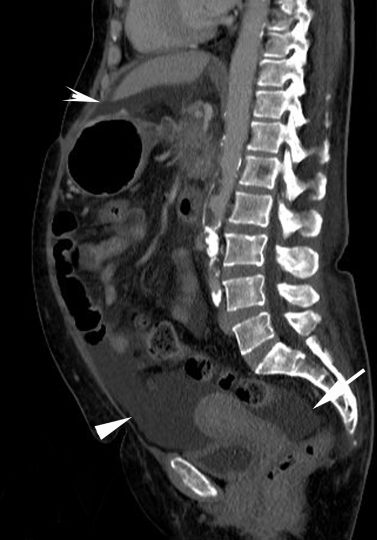

Au scanner, l’ascite apparaît comme un épanchement de densité liquidienne (entre 0 et environ 30 UH) ne se rehaussant pas après injection de produit de contraste (figures 4.2 et 4.3). En IRM, l’ascite présente un hypersignal en pondération T2, un hyposignal en pondération T1 qui ne se rehausse pas après injection (cf. figure 16.3).

Fig. 4.3 Reconstruction sagittale de l’examen tomodensitométrique de la figure 4.2 sur l’ensemble de l’abdomen et du pelvis.

L’ascite est visible autour du foie (tête de flèche creuse), dans le récessus recto-utérin (de Douglas) (flèche) montrant une ascite abondante (flèche) et dans la région hypogastrique (tête de flèche).

Source : CERF, CNEBMN, 2022.